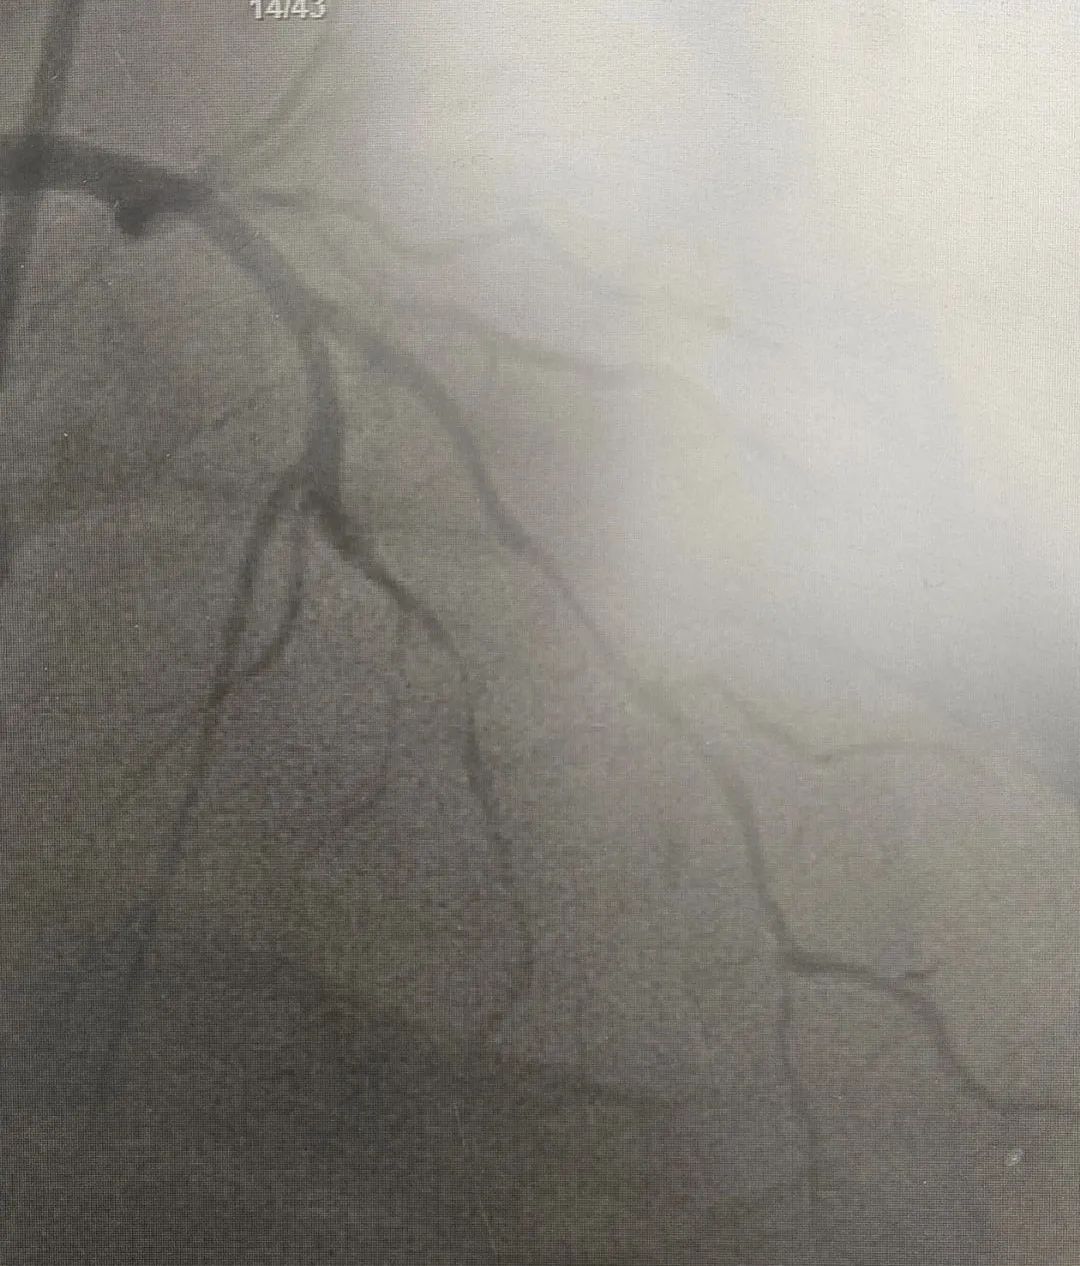

近日,玉山县黄家驷医院(玉山县人民医院)医护团队和玉山县博爱医院医护人员共同上演了一场“生命接力赛”,经过近7小时的救治,成功抢救一名呼吸心脏骤停、急性心肌梗死的重症患者。

10月17日,家住玉山县的何先生因胸闷气憋入住玉山县博爱医院,然而,在就诊过程中突发呼吸心跳骤停……医护人员立即予以心肺复苏、气管插管、电除颤等急救措施直至患者恢复自主心率,但意识仍丧失。考虑到患者病情危重,博爱医院医护团队与患者家属沟通后,即刻转至玉山县黄家驷医院(玉山县人民医院)继续救治。

发生急性心肌梗死,要采取就近抢救原则,及早送至有经皮冠状动脉介入治疗(PCI)能力的医院行PCI治疗,如就诊医院无法行PCI治疗,建议立即转至附近有PCI能力医院行PCI治疗或溶栓治疗,尽量缩短发病时间至开通闭塞血管的总缺血时间,总缺血时间越短,患者的生存率及康复率就越高。

我院胸痛中心为胸痛患者24小时开通生命“绿色通道”,早发现早诊断早治疗,能争分夺秒为患者开通闭塞血管,挽救濒死的心肌,缩小梗死的面积,保护心脏功能,及时处理心肌梗死的各种并发症,是玉山及周边地区心梗患者救治的较佳选择。

自 2021 年 4 月我院启动胸痛中心建设以来,全院上下高度重视、全员动员,有序地推进各项工作的开展,胸痛中心建设工作不断完善,于2023年8月通过国家级胸痛中心认证,成为国家级胸痛中心的一员。这标志着我院对急性心肌梗死等高危胸痛的救治水平、流程优化、硬件设施等方面均已达到国家级标准。

在推进胸痛中心建设中,我院严格做好有指征的筛查工作,就诊的病人在增加,冠脉介入术数量在增加,介入自主完成率也越来越高(急性心梗介入手术自主完成率达100%),心梗患者在本地发现率、救治率均明显提升,获得了明显的社会效益。在全市的排名中:2024上半年,急性心梗收治100例,冠脉介入手术120例,两项均位列全市第二名,仅次于上饶市人民医院,已领先于同级县医院。